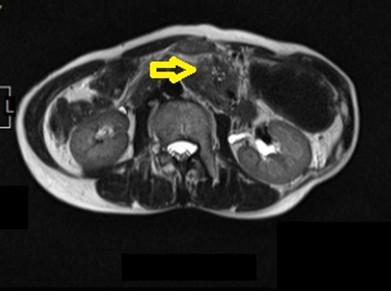

@膵がんの症例;無症状でしたが肝臓にも転移しているStage IVでした。

@先ほどの症例のMRCP画像。膵管の拡張がありました。